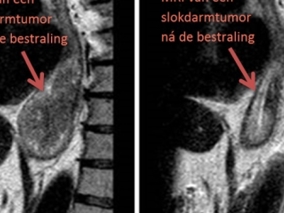

Deze grafieken laten zien hoeveel patiënten leven vijf jaar na de diagnose

Hierboven ziet u de zogeheten ‘relatieve overleving’. Bij deze berekening wordt rekening gehouden met het feit dat patiënten ook om andere redenen dan kanker kunnen overlijden. De overleving is gecorrigeerd voor de levensverwachting. Zo wordt duidelijk wat het effect van kanker zelf is.